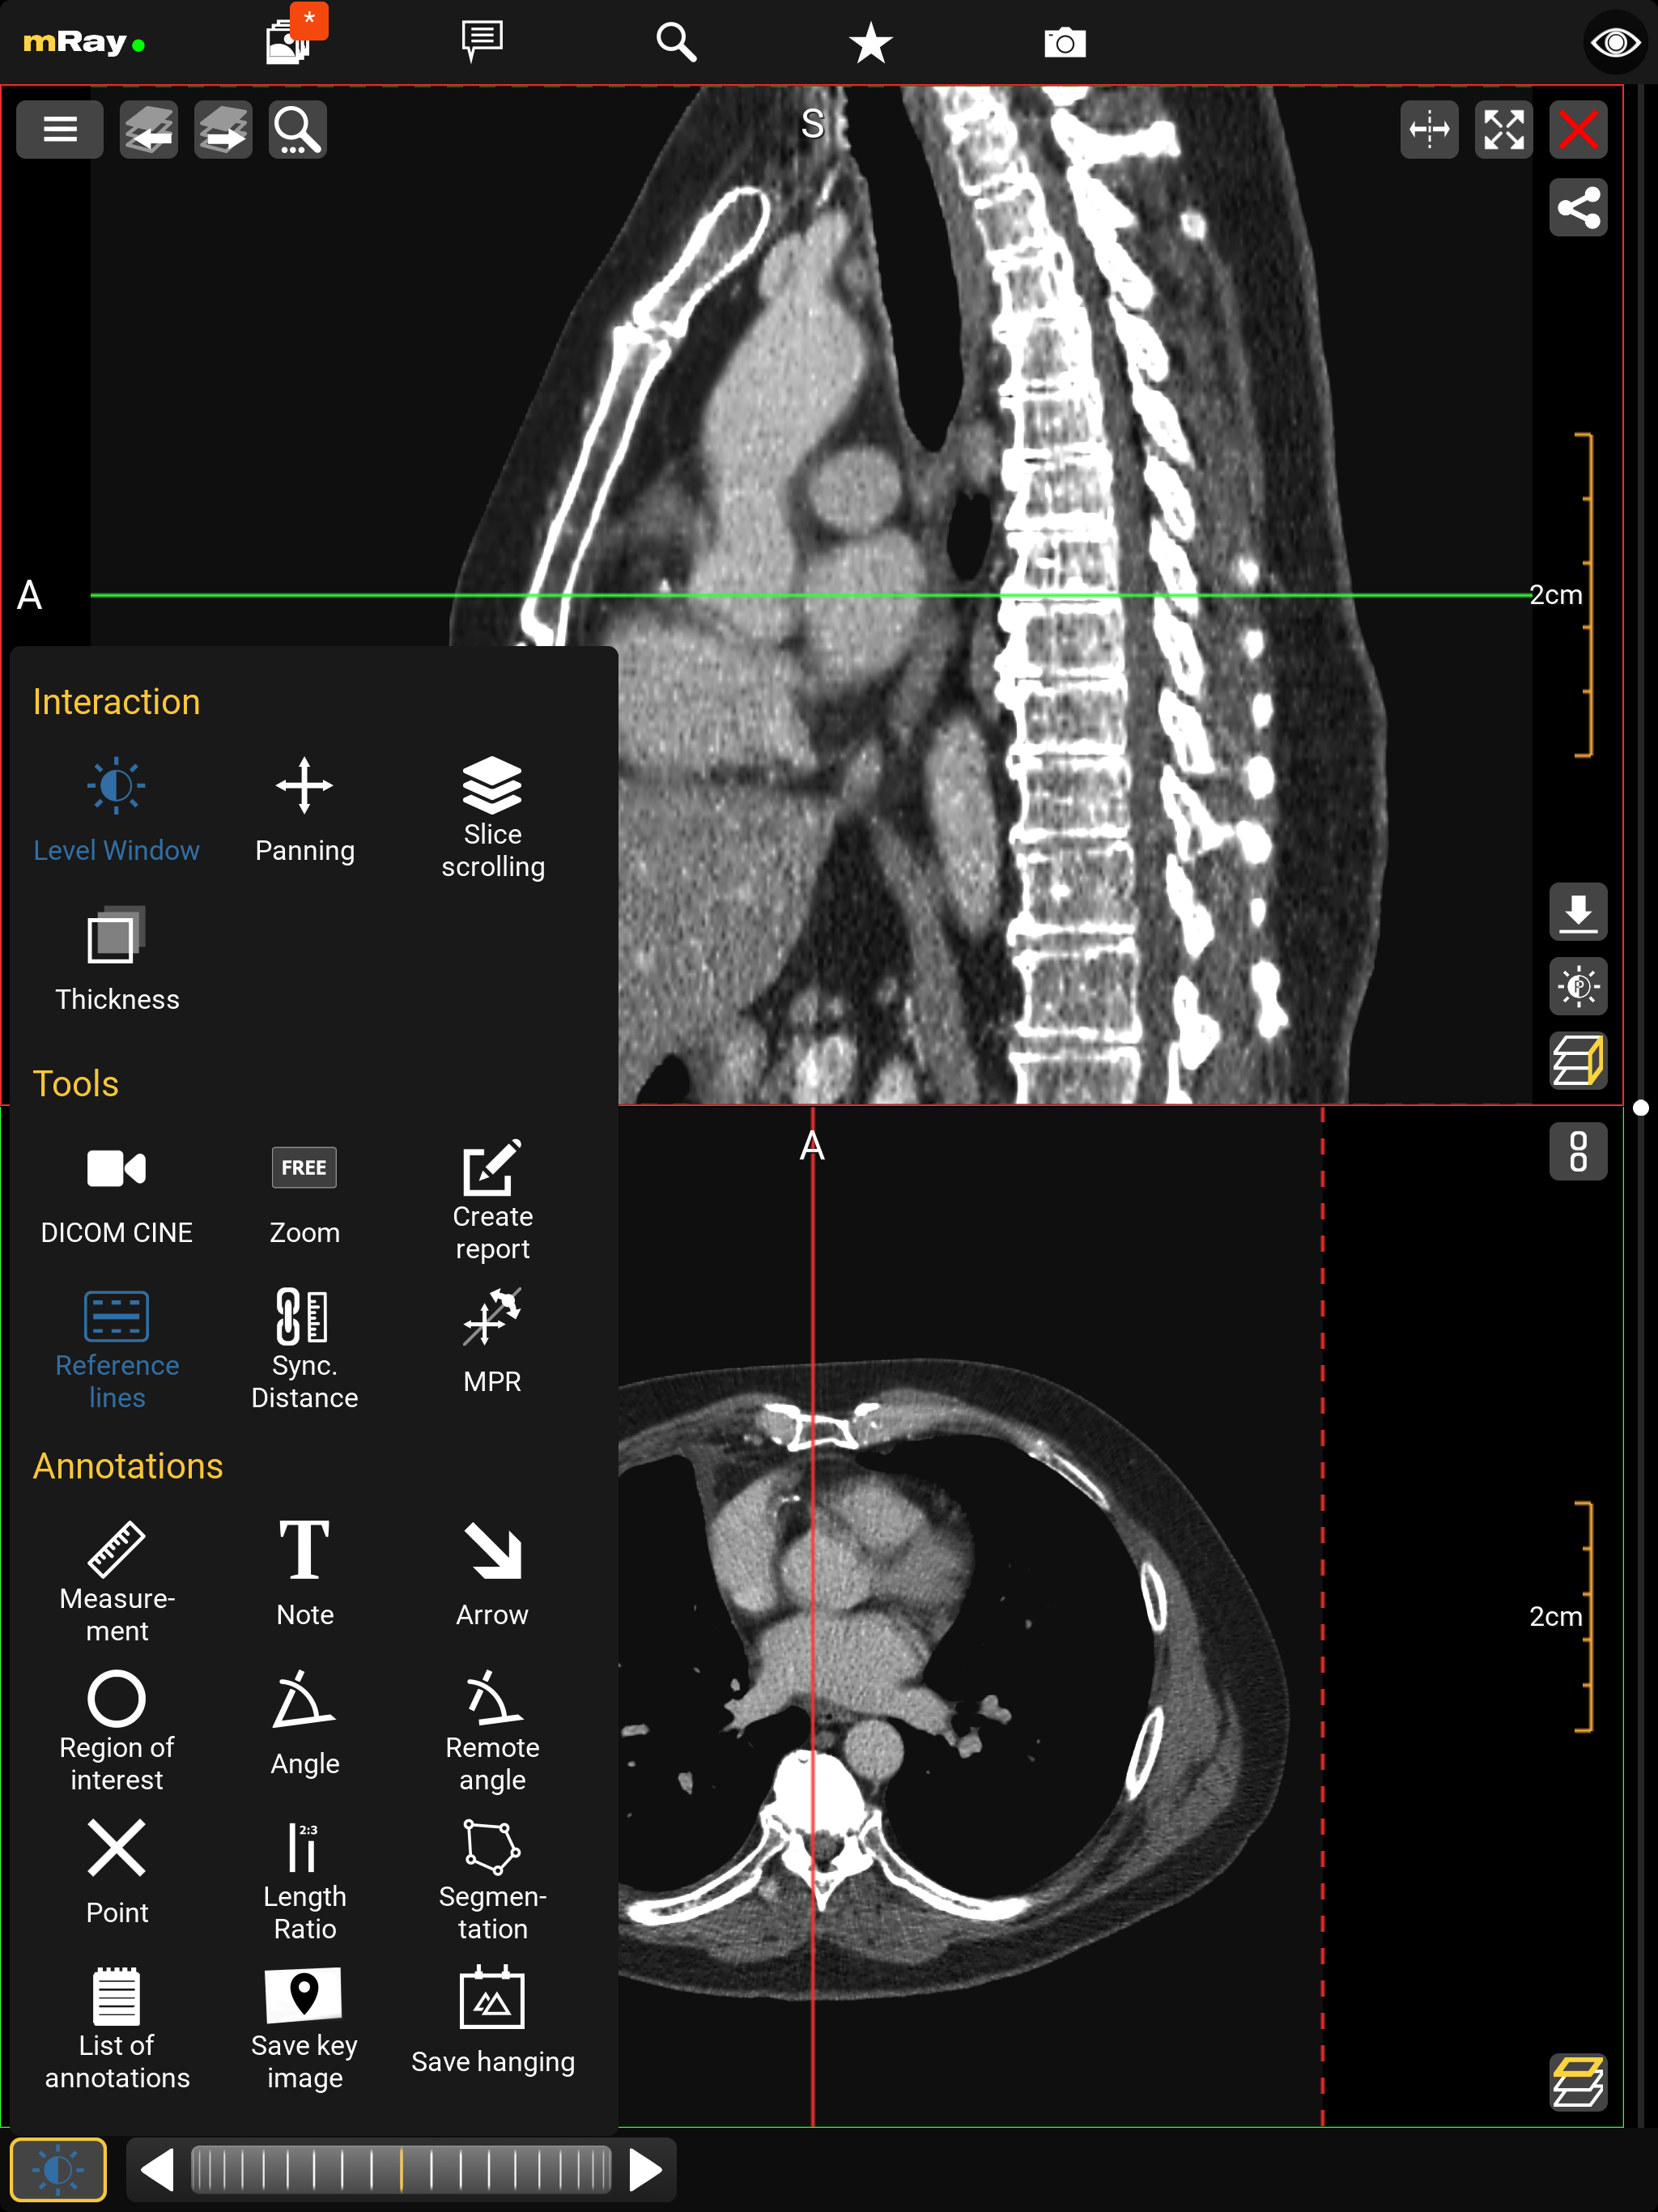

10.5. Werkzeugmenü

Über das Werkzeugmenü können Sie folgende Werkzeuge auswählen:

-

Interaktionen

-

Level Window: Über das Level-Window können Sie die Grauwerte und die Helligkeit der Anzeige anpassen (Fensterung).

-

Verschieben: Über das Panning können Sie das Bild verschieben, vergrößern und verkleinern. Dies ist standardmäßig ausgewählt.

-

Schichten blättern: Über das Slice scrolling können Sie durch die Schichtbilder blättern (siehe Interaktionsleiste und Scrollbar). Das Scrollen passiert über vertikale Bewegungen auf dem Bild mit gedrückter linker Maus oder durch Touch.

-

Schichtdicke: Maximum Intensitätsprojektion (MIP). Über diese Funktion ist es Ihnen möglich, mehrere Schichtbilder auf einmal zu betrachten. Dafür werden bis zu 11 Schichten transparent übereinander gelagert.

-

-

Werkzeuge

-

DICOM Cine: Ermöglicht das Abspielen von DICOM Cine Dateien oder 3D Datensätze.

-

Zoom: Zoomen Sie das Bild rein und raus im voreingestellten "FREE" Modus. Durch das Auswählen des Zoom-Tools im Werkzeugmenü können Sie auf eine der vorgefertigten Zoomstufen in den folgenden Formaten wechseln: 1:1, 1:2, 1:4 und "FREE".

-

Bericht erstellen: Öffnet den Dialog um, parallel zur Bildbetrachtung, einen Befundbericht zu erstellen.

-

Referenzlinien: Wechselt zwischen den verschiedenen Darstellungsmodi für Referenzlinien.

-

MPR Zeigt alle MPR-Ansichten des aktiven Datensatzes an und ermöglicht die Ebenensteuerung durch Ziehen von Referenzlinien. (Beliebig orientierte MPR)

-

SyncAlign Richtet automatisch eine oder mehrere der verfügbaren Datensätze anhand der Patientenposition aus. (Synchronisierte Ausrichtung)

-

Volumen-Rendering Visualisiert den Datensatz der aktiven Ansicht als ein dreidimensionales Volumen. (Volumen-Rendering)

-

-

Annotationen

-

Messung: Lässt Sie Messungen auf der aktuellen Schicht vornehmen.

-

Notiz: Über diese Funktion können Sie Notizen auf der aktuellen Schicht erstellen.

-

Pfeil: Dieses Tool lässt sich nutzen, um kritische und wichtige Stellen innerhalb eines Bilddatensatzes zu markieren und aufzuzeigen.

-

Region of Interest: Mithilfe dieser Funktion kann eine Region der aktuellen Schicht elliptisch umgrenzt werden, welche gleichzeitig wichtige Informationen bezüglich des umkreisten Pixelbereichs zurückliefert.

-

Winkel: Mit diesem Tool können Sie Winkelmessungen auf der aktuellen Schicht vornehmen.

-

Entfernter Winkel: Erlaubt die Messung von entfernten Winkeln durch zwei getrennte Geraden.

-

Punkt: Über diese Funktion können Sie Kreuze auf der aktuellen Schicht erstellen.

-

Längenverhältnis: Zeigt das Längenverhältnis zwischen zwei Geraden.

-

Segmentierung: Erzeugen Sie eine manuelle Segmentierung.

-

Schlüsselbild speichern: Lässt Sie die aktuelle Schicht samt Notizen und Messungen in der Serie speichern. Die Schicht in Ihrer Ausgangsform bleibt dabei erhalten.

-

Als Hanging speichern: Speichern Sie die aktuelle Position und Orientierung der Schichten aus allen Ansichten zur späteren Verwendung.

-

Liste der Annotationen: Enthält alle Annotationen die Sie hinzugefügt haben. Wenn Sie eine Annotation aus der Liste lange drücken, werden weitere Optionen wie Mehrfachauswahl, Umbenennen und Löschen angezeigt.